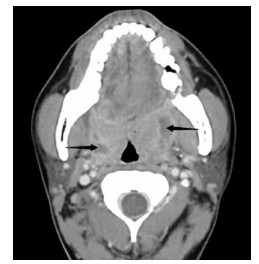

1 资料与方法患者,男,22岁,因“咽痛16 d ”于2020年6月19日就诊于浙江大学医学院附属第二医院耳鼻喉科。起初未就医,近半个月来咽痛逐渐加重,伴左侧耳朵放射痛,吞咽时明显,不能言语,伴张口困难,进食困难,夜间平卧时偶感呼吸不畅。来院前1 d,患者曾有吐出脓血性液体。查体见张口度1.5指,双侧软腭隆起,充血,双侧扁桃体Ⅱ度,右侧扁桃体后方可见少许脓液流出。急诊行颈部增强CT(图 1)示:双侧扁桃体炎伴周围脓肿形成,右侧脓腔可见积气。尝试行左侧扁桃体周围脓肿穿刺,未及明显脓液。收住入院后予头孢哌酮舒巴坦抗感染及甲泼尼龙抗炎消肿治疗,患者感咽痛逐渐缓解,软腭肿胀逐渐减轻。入院后第5天,再次行颈部增强CT(图 2)示:左扁桃体脓肿扩大,右侧扁桃体内脓肿消失,局部轻度肿胀。予行左侧扁桃体周围脓肿穿刺及切排,流出较多脓液。切排后,继续予上述药物治疗,每日定期扩张切排口,入院后第7天,切排口已无明显脓液,复查颈部增强CT(图 3)示:左侧脓肿基本吸收、残留少许气体。入院后第8天,患者予出院。后经短期随访,患者恢复情况可,无症状反复。目前患者已失随访,本研究经医院伦理委员会审批免除知情同意,批件号:(2020)伦研审第(979)号。

| 图 3 患者2020-06-28颈部C增强CT(箭头示左侧扁桃体周围脓腔吸收) |